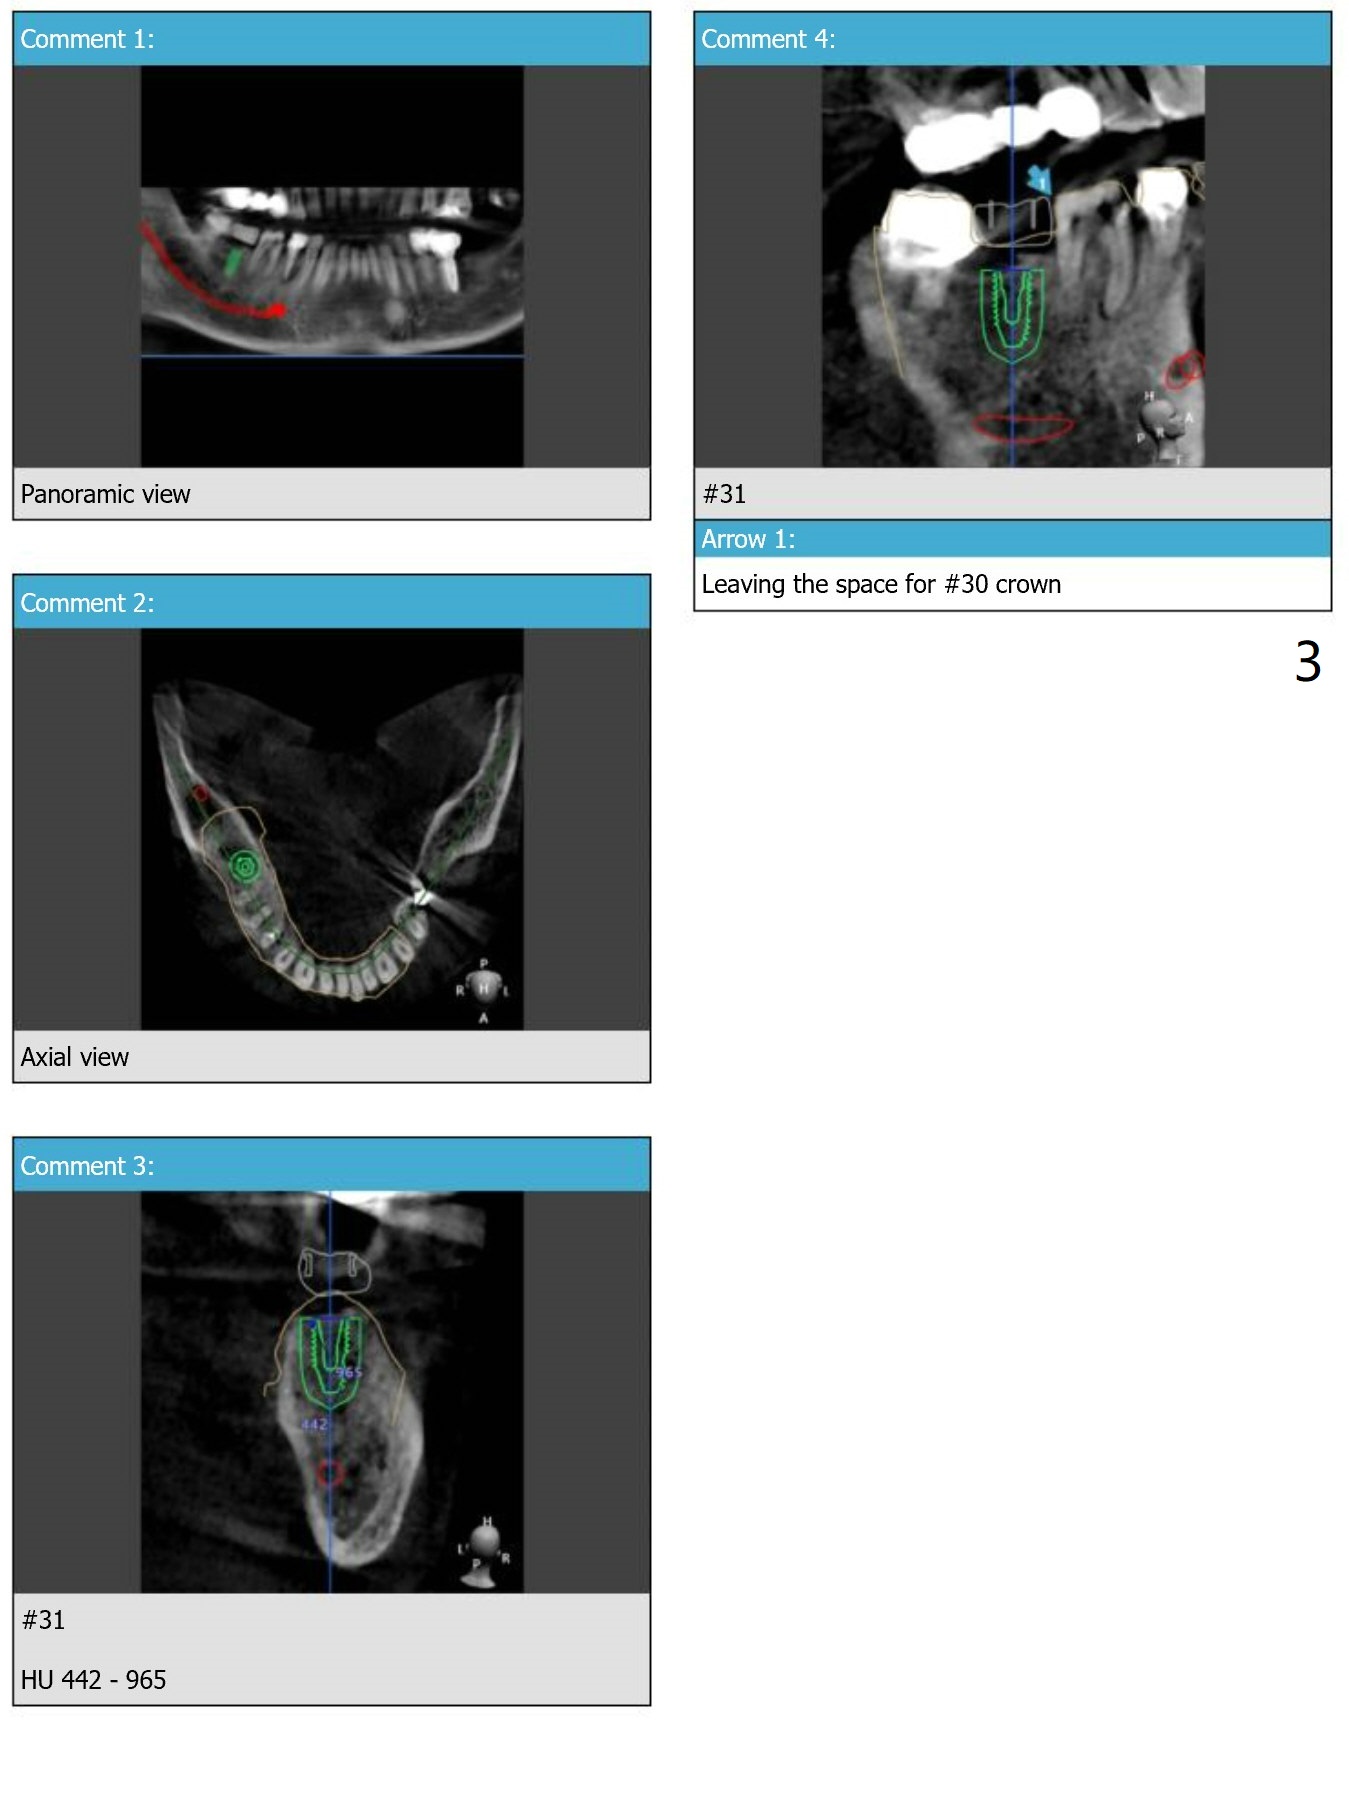

Crestal Level

The distal crest is lower than the mesial one. The 5x10 mm implant is level with the distal crest (Fig.2).